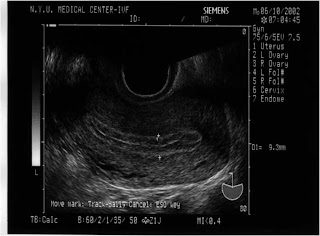

Endometrial hyperplasia occurs when the endometrium, the lining of the uterus, becomes too thick. It is not cancer, but perform diagnostic tests for endometrial hyperplasia and cancer. Transvaginal ultrasound may be done to measure the thickness of the endometrium. For this test, ... Fetch Document